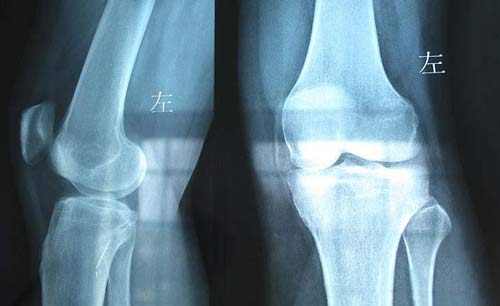

(图:患者膝关节骨质增生,关节疼痛不能下地)

吴阿姨到院后,主治医生经过问诊、检查并结合我院全力独家引进的HD-热层析检测系统检查,诊断吴阿姨现在为风湿性关节炎中晚期,并且还有病情加重的趋势。根据问诊患病史,主治医生了解到吴阿姨早期被误诊为骨关节炎,误诊错误治疗后导致四肢关节疼痛红肿加重。现在检查结果显示:类风湿因子39 IU/ml,超敏C反应蛋白62mg/L。全身关节胀痛,以手肘关节、膝关节、踝关节疼痛较重,膝关节红肿严重,下蹲困难,行走能力受限。